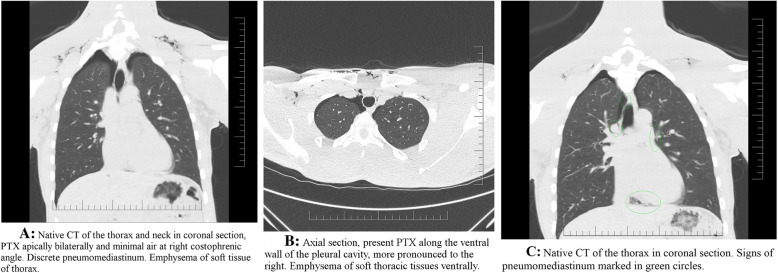

The first chest X-ray and CT showed diffuse emphysema of the superficial and deep parts of the neck, continuing to the proximal section of the ventral chest wall (Fig. 3a, b). Diffuse pneumomediastinum signs are apparent paratracheal right, around right pulmonary artery, junction of left pulmonary veins and left atrium further are present signs in right cardiophrenic angle (Fig. 3c). A small bilateral pneumothorax was found apically and basally with pneumoperitoneum. The pneumoperitoneum was concluded to have been caused by passing gas through the hiatus in the diaphragm. There was no evidence of free fluid in the chest, no dislocations of mediastinal structures, no traumatic skeletal changes. A bronchoscopy was recommended for suspected airway injuries, but the patient refused. Conservative protocol without thoracic drainage was followed during his hospital stay. A two-day interval chest CT scan showed regression of the bilateral pneumothorax, regression of soft tissue emphysema, as well as pneumomediastinum regression. The patient stated he felt well and did not exhibit any additional symptoms, so he was discharged. After the discharge, follow-up examinations were recommended and a 2 month no-fly period was ordered. However, after 3 days, the patient left to his homeland and a contact at required medical level was lost. Pilot reported that he is doing well, without any problems and will be fit-to-fly soon.

Fig. 3.

a Native CT of the thorax and neck in coronal section, PTX apically bilaterally and minimal air at right costophrenic angle. Discrete pneumomediastinum. Emphysema of soft tissue of thorax. b Axial section, present PTX along the ventral wall of the pleural cavity, more pronounced to the right. Emphysema of soft thoracic tissues ventrally. c Native CT of the thorax in coronal section. Signs of pneumomediastinum marked in green circles